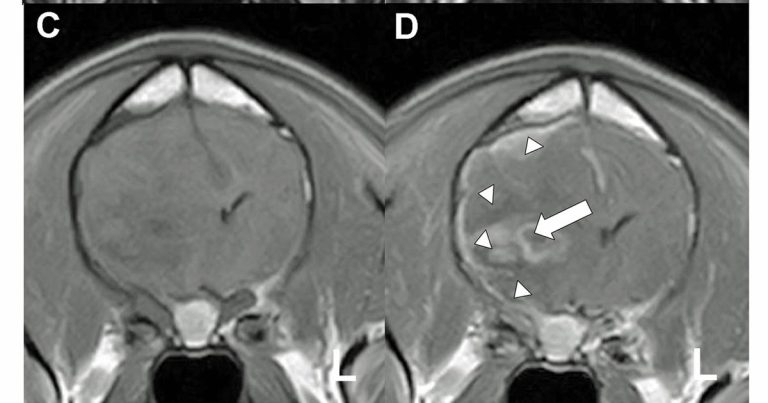

Postictal imaging abnormalities are sometimes seen on MRI during this time and appear to be reversible (Figures 2 and 3; Mellema et al, 1999).